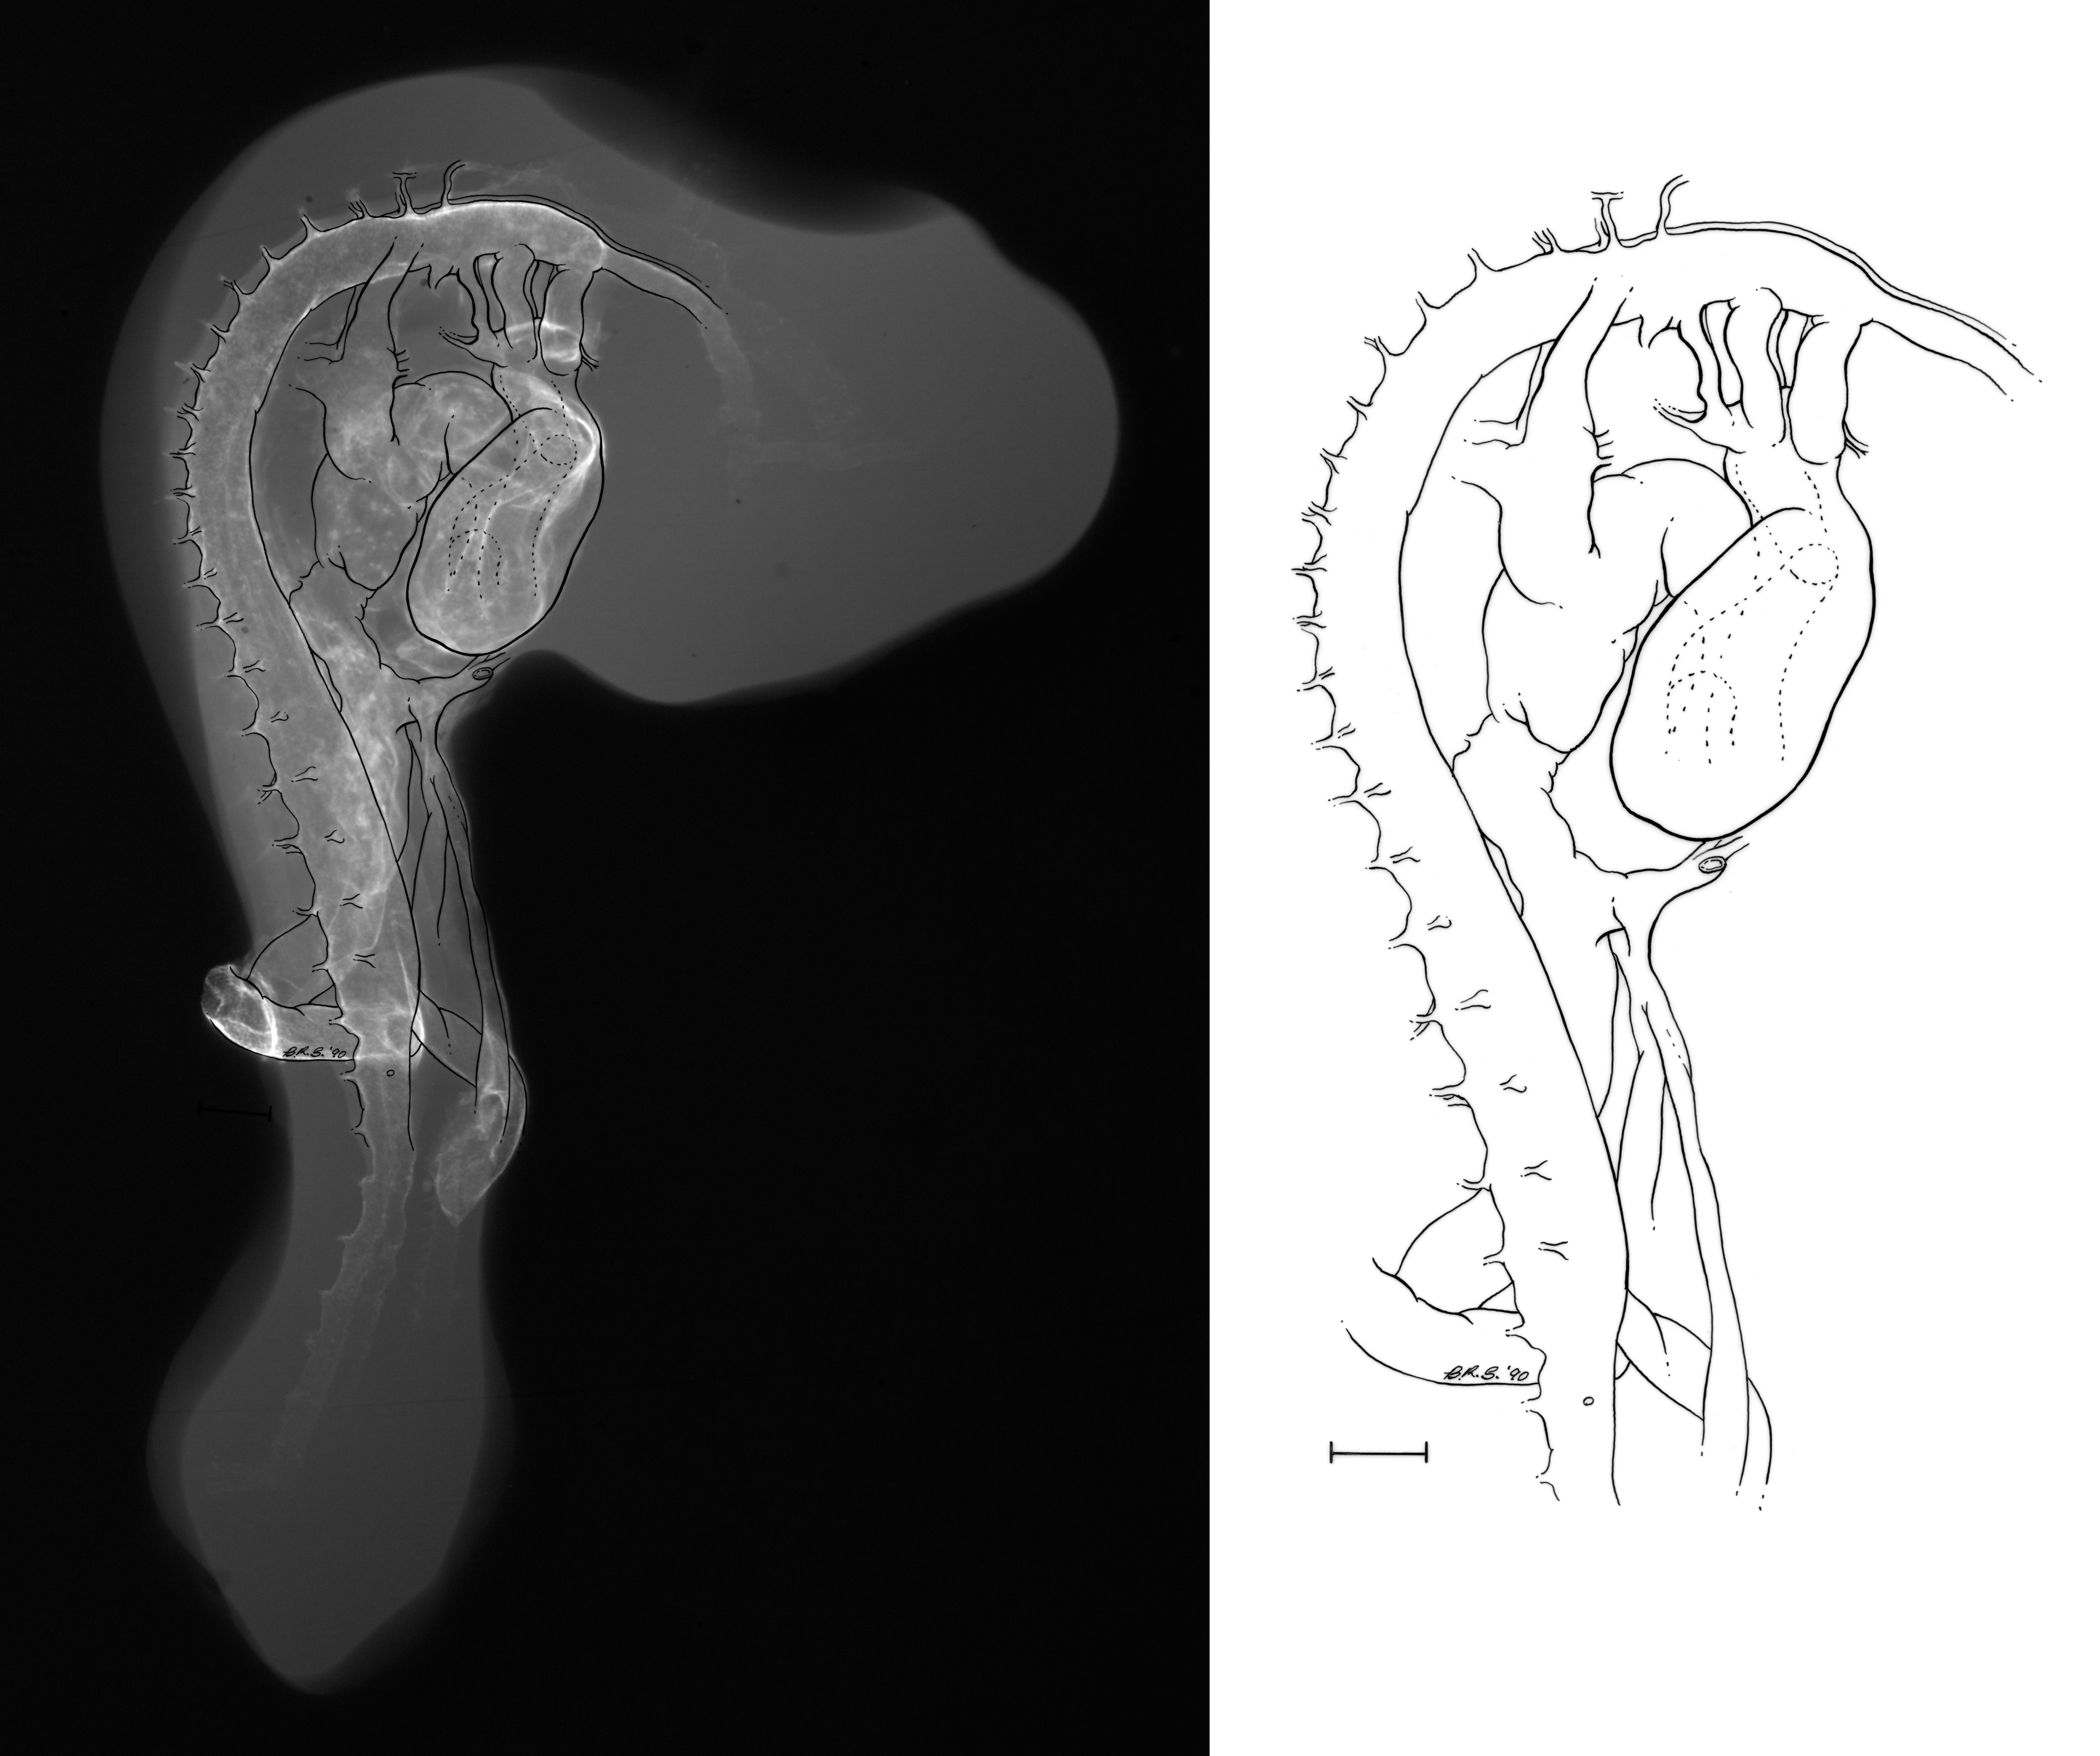

Chick Embryo Microangiography

Hamburger-Hamilton (HH) Stage 18 (approx. 3 days)

X-Ray Micrographs

Drawing